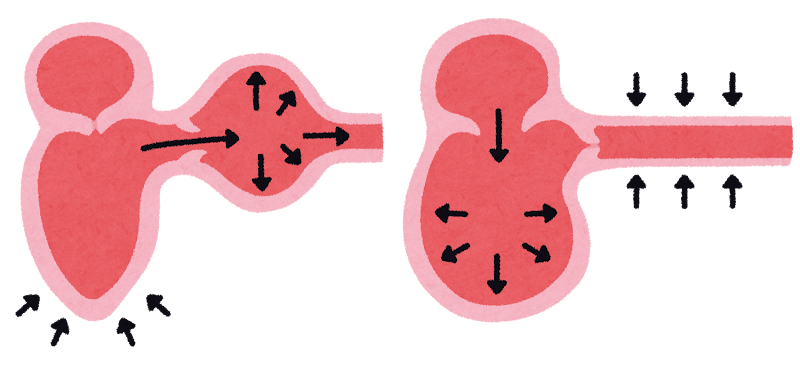

血圧測定

高血圧は、腎臓・目・脳・心臓にダメージを与える全身性の問題です。

腎臓病では高血圧を伴うことが多く、合併症予防のためにも重要です。

血圧が高い状態が続くと、腎臓に負担がかかり、腎機能低下がさらに進行してしまいます。

また、高血圧は食欲の低下や視力や心臓への影響を引き起こすこともあります。